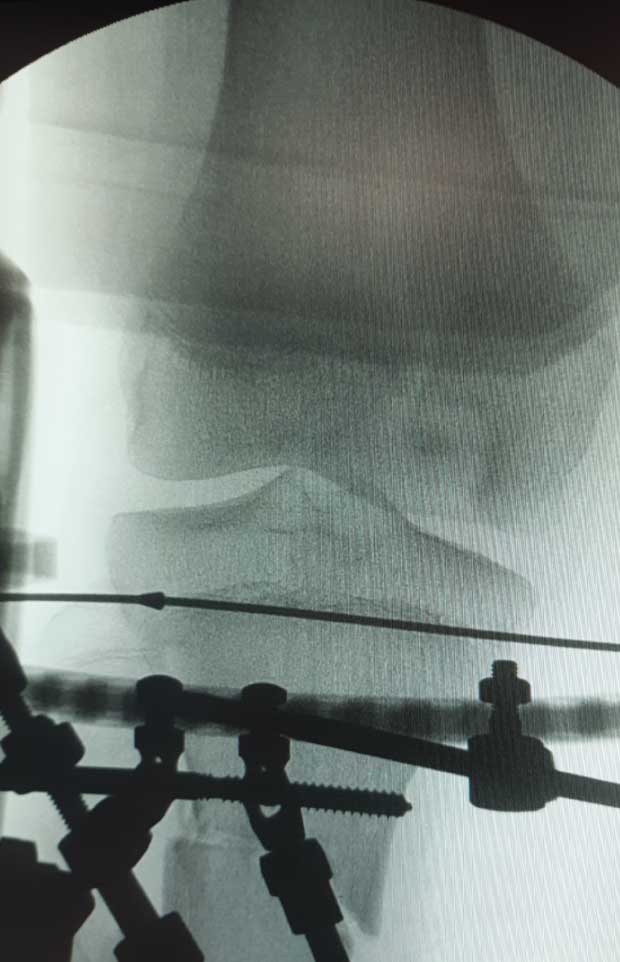

Caso No. 10 - Luxofractura de tobillo

Preoperación

Posoperación

Diagnóstico: Luxofractura de tobillo

Rx de perfil transoperatoria

Rx transoperatoria anteroposterior

Tratamiento: Cirugía: reducción abierta y fijación interna